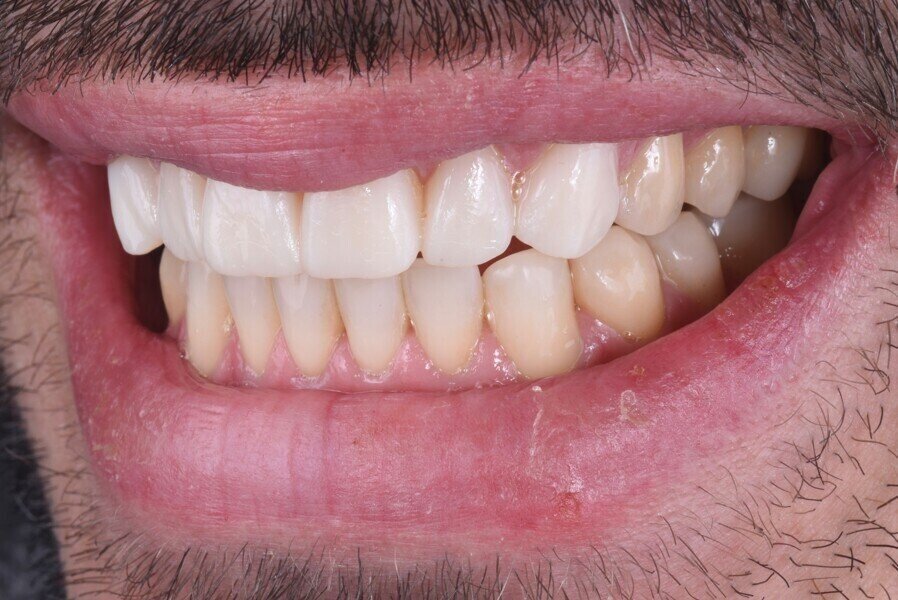

Do naší ordinace přišel 42letý muž, který doufal ve vylepšení svého úsměvu. Byl si vědom opotřebení chrupu v předním úseku a také některých zadních zubů. Tato situace vedla k obnažení značné oblasti dentinu, což způsobilo vysokou citlivost a negativně ovlivnilo estetiku jeho úsměvu (obr. 1). Dále se u něj projevilo určité stěsnání a vztah stoliček III. třídy, což mělo za následek určitou modifikaci okluze, tendenci ke vztahu řezáků III. třídy a skus hrana na hranu (obr. 2).